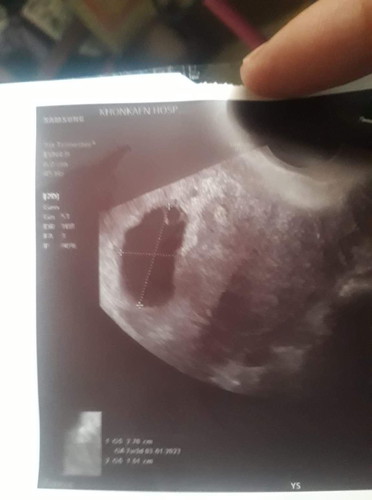

คุณแม่ท่านไหนเป็นบ้างค่ะ น้องมีอายุครรภ์ 10สัปดาห์ แต่หาเด็กยังไม่เจอ หมอนัดอิก 2อาทิตสุดท้าย กลัวจังเลย ขอข้อมูลหน่อยจ้า

ของเราเจอตอน10สัปดาห์ หัวใจเต้นตุบๆ ดิ้นเป็นม้าน้ำเลย ขอให้เจอตัวเล็กนะคะรอก่อนให้ถึง12สัปดาห์